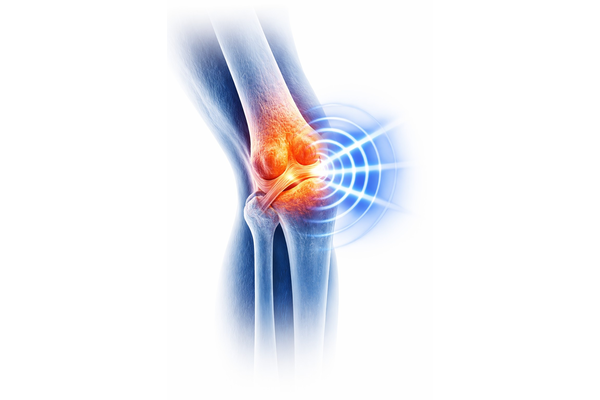

Experience Freedom From Pain

Our cutting‑edge physiotherapy and regenerative therapies help you regain mobility and live pain‑free. Begin your healing journey today across Telangana and beyond.